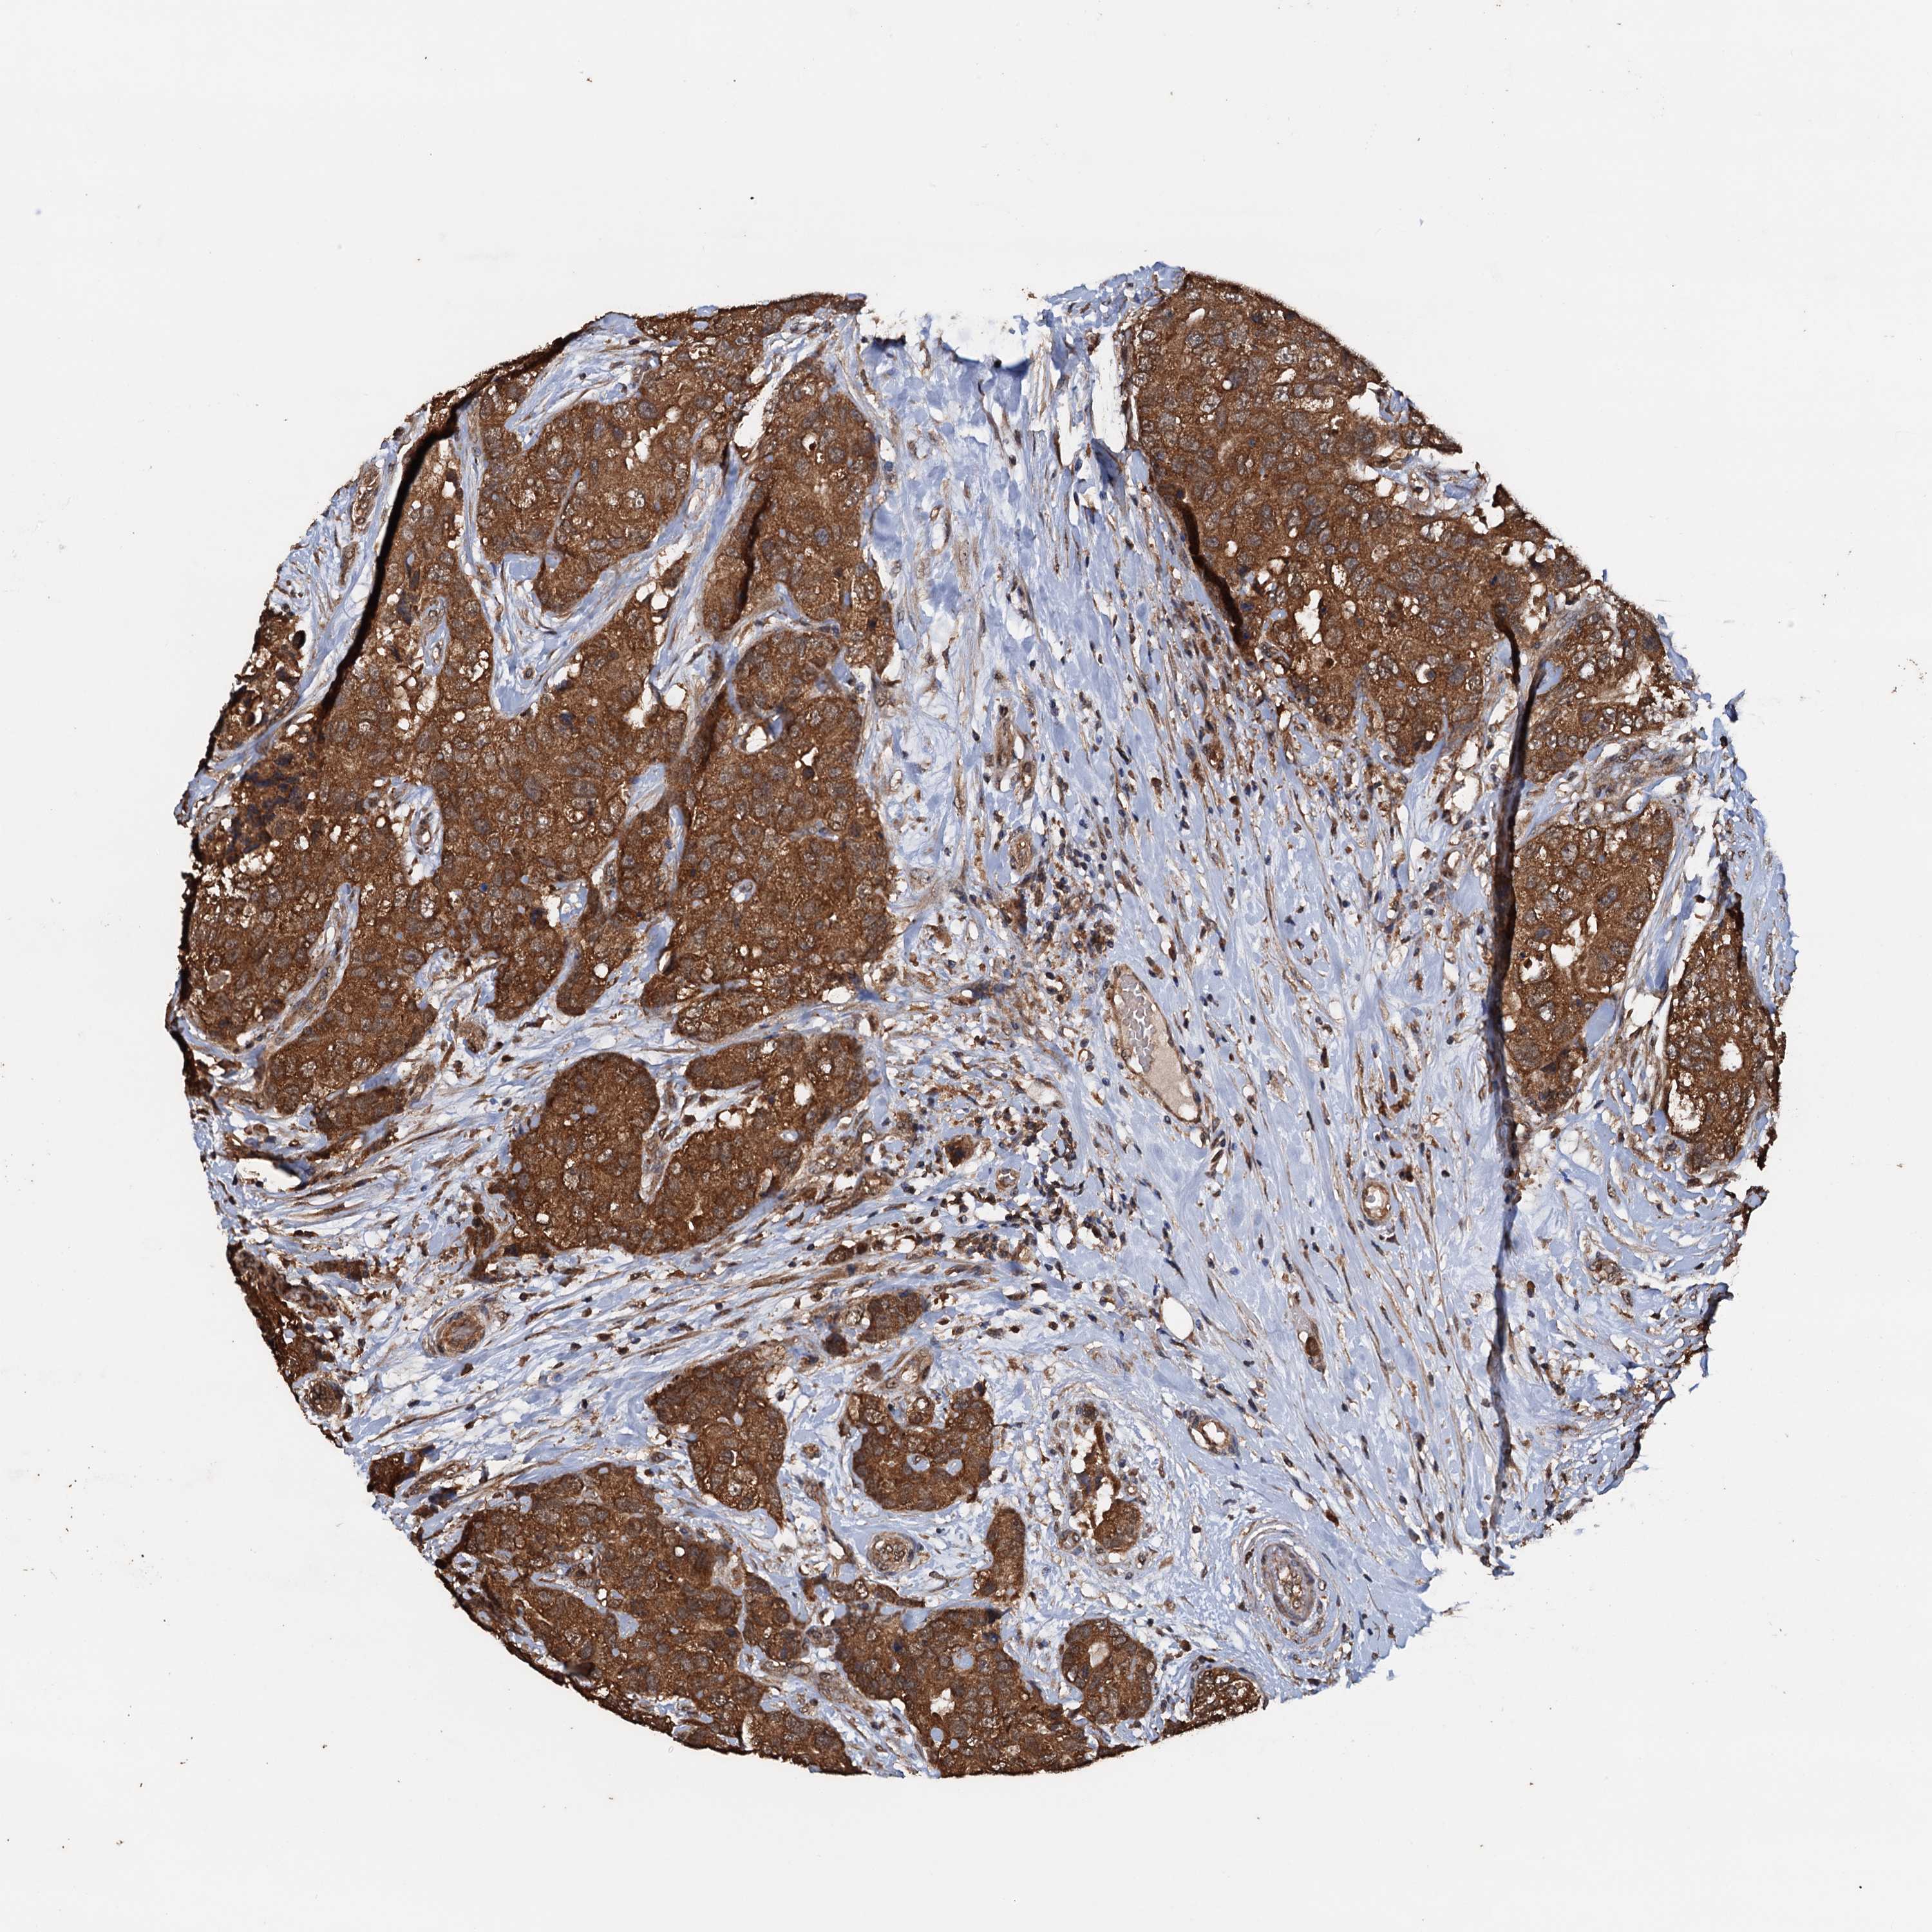

CANCER BREAST CANCER Show tissue menu

BRCA TCGA BRCA VALIDATION PROTEIN EXPRESSION

Breast cancer

Human cancer